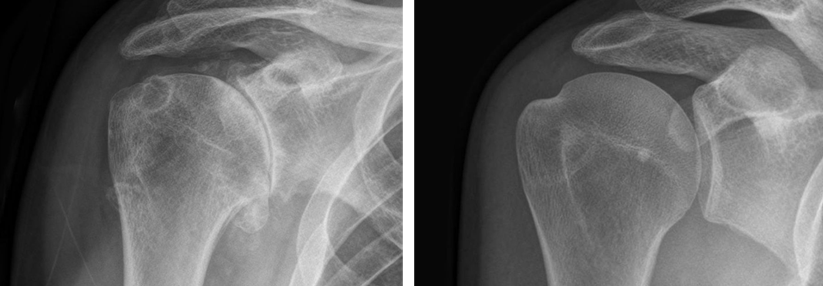

Arthrosen schädigen vor allem die End- und Mittelgelenke (DIP- bzw. PIP-Gelenke), entzündlich-rheumatische Erkrankungen eher die Fingergrundgelenke (MCP-Gelenke), erklärte Dr. Stephan Schindele, Handchirurg von der Schulthess Klinik in Zürich. Vor dem Griff zum Skalpell steht meist der Versuch, die Beschwerden mit konservativen Maßnahmen wie Steroidinfiltrationen, Radio­nuklidbehandlung und Bestrahlung zu lindern.